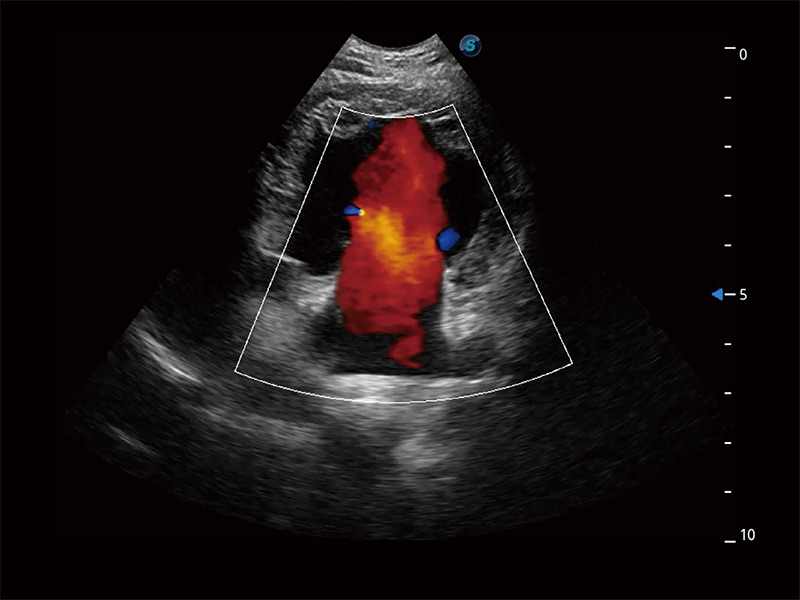

極大提升超低速微細(xì)血流的檢出能力,同時(shí)更精準(zhǔn)地濾除軟組織和超聲信號(hào),為獸用醫(yī)生提供以往無法通過常規(guī)血流獲得的疾病診斷信息。

在傳統(tǒng)二維血流成像的基礎(chǔ)上,呈現(xiàn)血流的立體感,具有動(dòng)感的生命力之美。即便是微小的血管也能輕松應(yīng)對(duì),提高了血流的視覺敏感性。